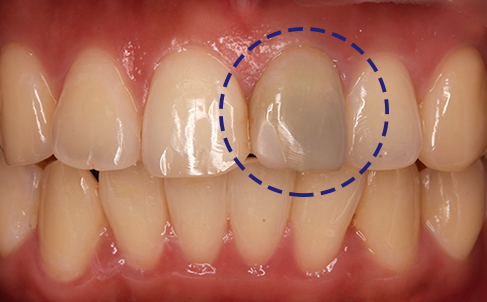

Trauma

Physical damage to the teeth can lead to the internal staining of teeth. This can happen when blood cells break down internally, causing discoloration from the inside.

Patients who have white spots on their teeth are generally advised against undergoing teeth whitening procedures, as these treatments can make the white spots even more noticeable. This is because the whitening process uniformly lightens the color of the entire tooth surface, thereby exaggerating the contrast between the normal tooth enamel and any white lesions present. Instead, dental veneers are recommended as a more suitable solution for such cases.

White spots are more prominent after whitening

Other treatments like MINISH Veneers are ideal

If the color of the teeth changes to gray or dark brown due to the hemoglobin component of the blood component in the pulp (nerve), tooth whitening is necessary.